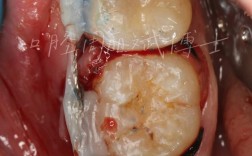

- 切口与翻瓣: 在缺牙区牙龈上做切口,翻开软组织,暴露骨缺损区域。

- 骨缺损处理: 清理骨缺损区域。

- 放置骨移植材料: 根据选择的植骨类型,将骨移植材料填充到缺损区域。

- 放置屏障膜(如需GBR): 覆盖骨移植材料,引导骨再生。